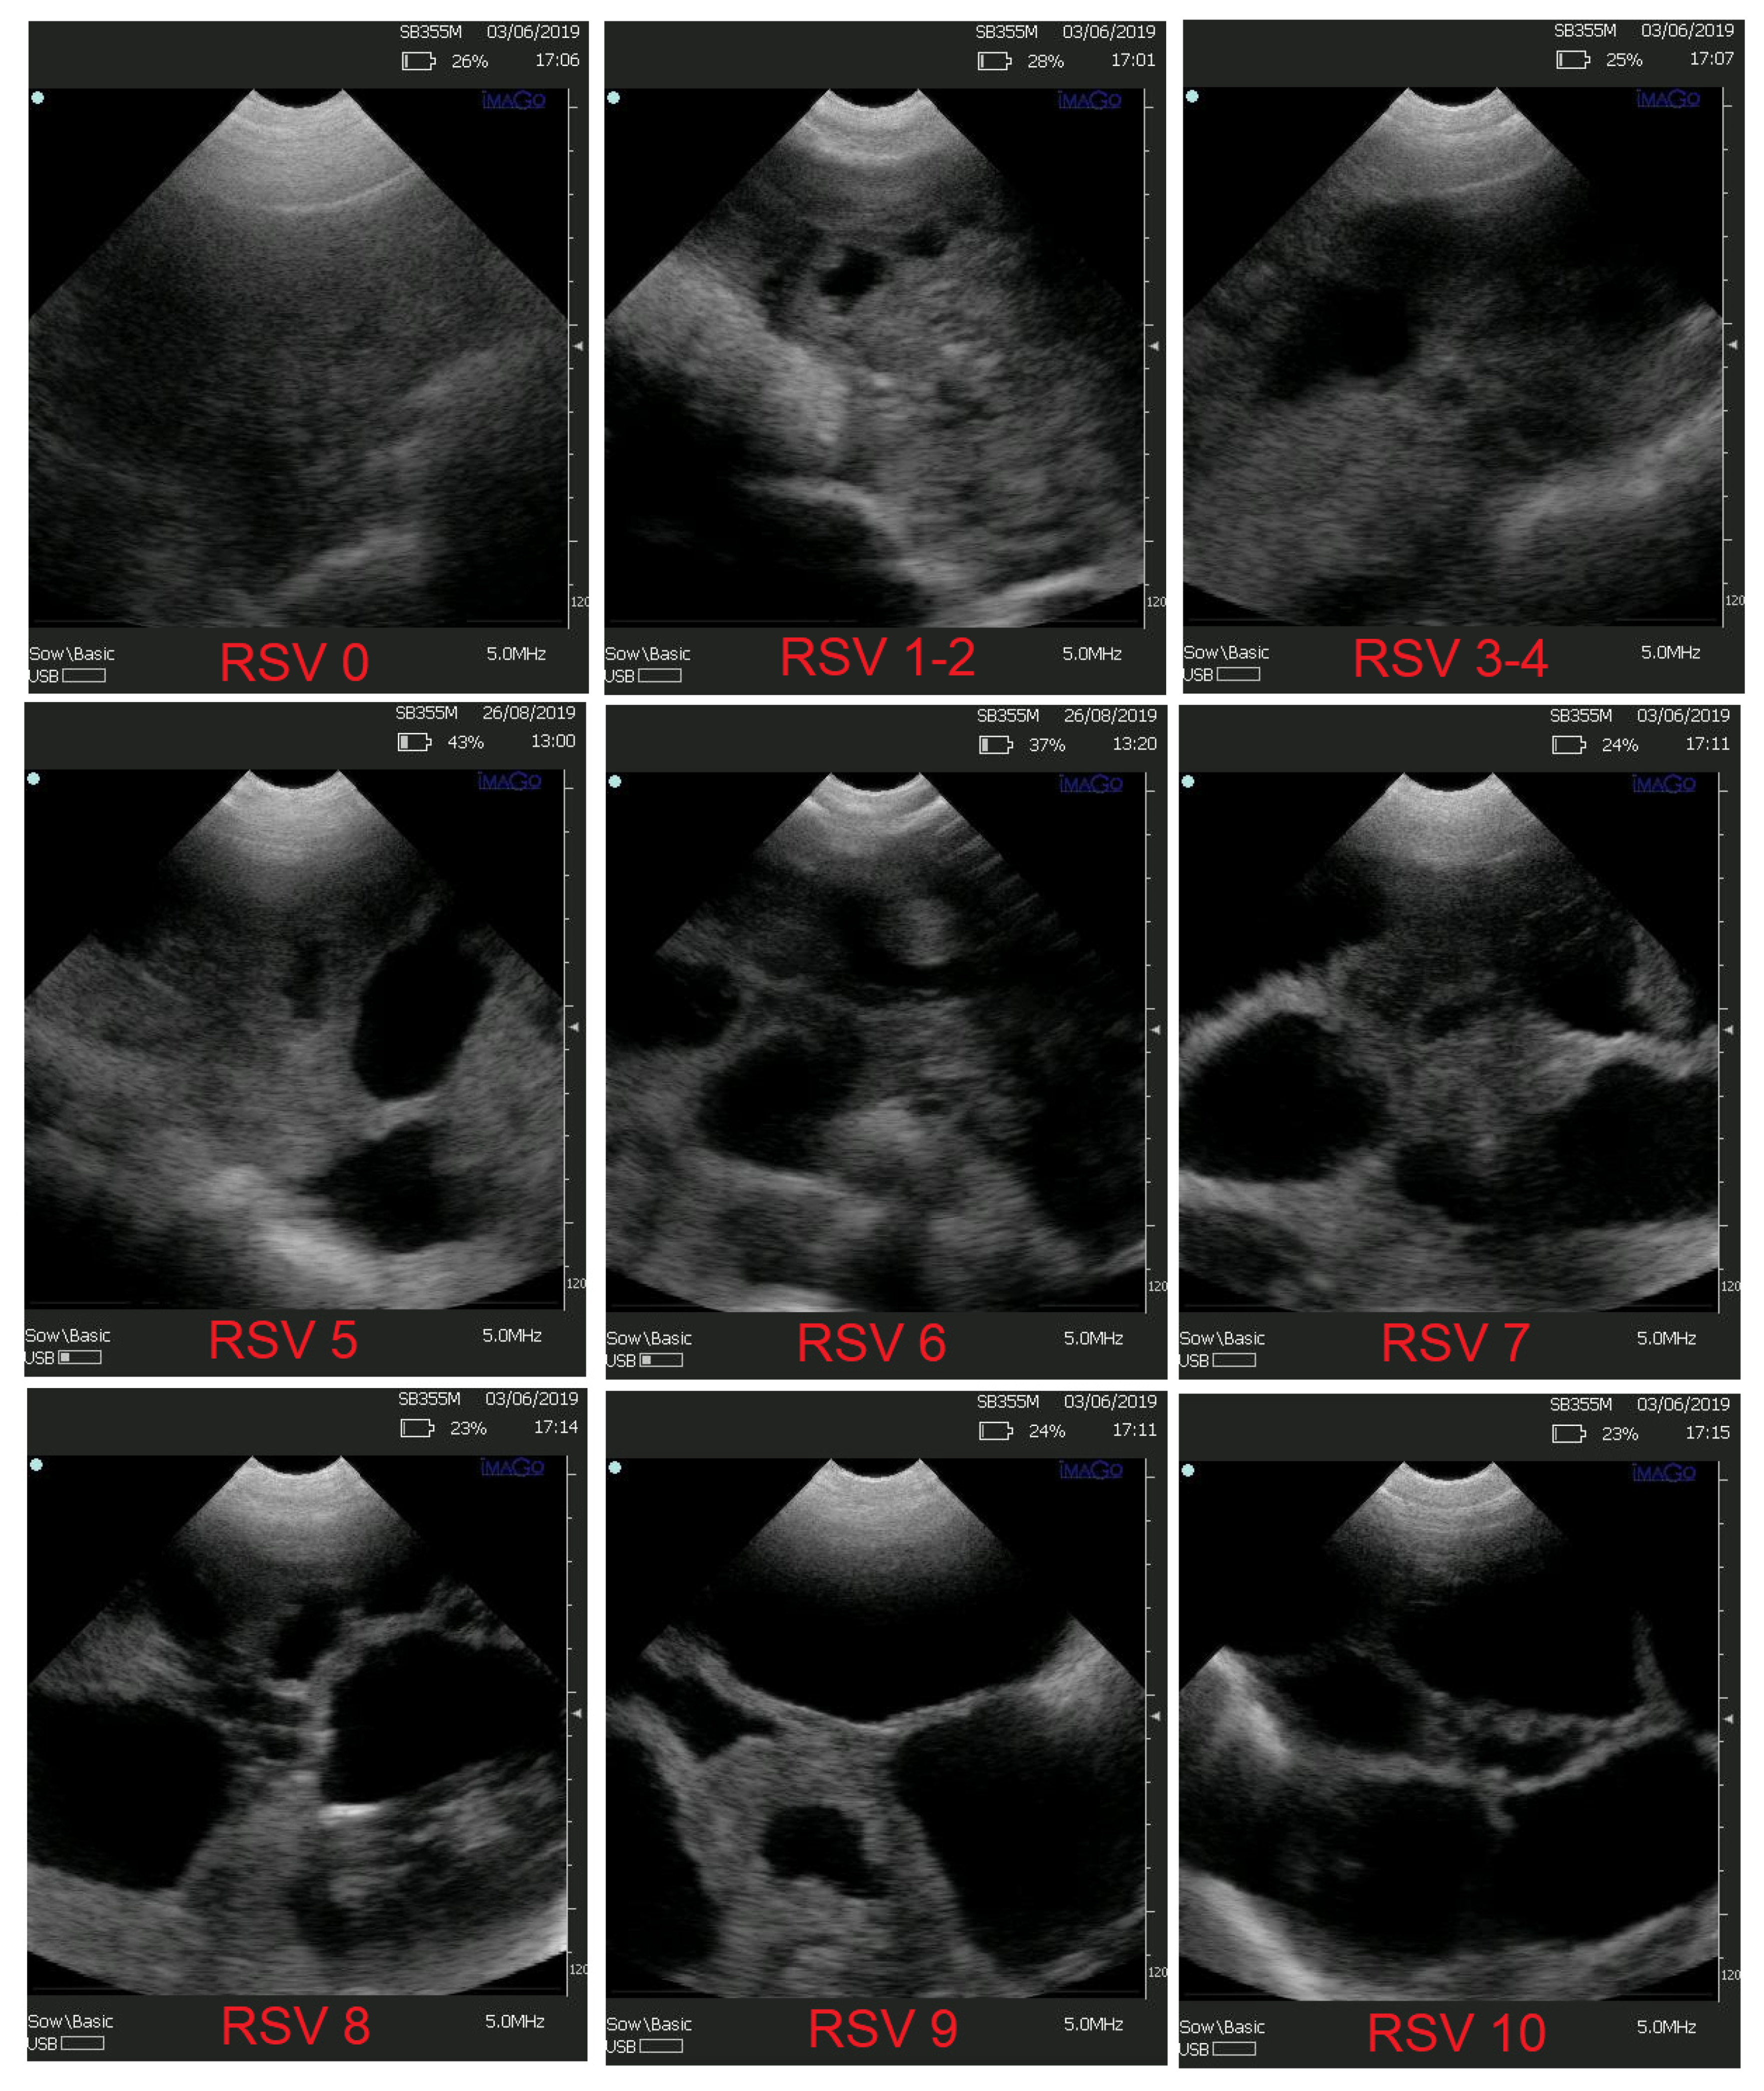

Figure A1.

The 10-point rating scale for the pregnancy diagnosis estimation. RSV = 0: complete absence of pregnancy indications, RSV = 1–2: low suspicion for pregnancy-typical image within 20 days post-insemination, RSV = 3–4: reasonable suspicion for pregnancy-typical image within 20–24 days post-insemination, RSV = 5: guaranteed pregnancy with possible small litter size, RSV = 6: guaranteed pregnancy of medium litter size, RSV = 7: guaranteed pregnancy with possible larger litter size, RSV = 8: guaranteed pregnancy of satisfactory litter size, RSV = 9: guaranteed pregnancy of possibly great litter size—typical image at least 25 days post-insemination, RSV = 10: great litter size. Adopted from: 17. Kousenidis, K.V.; Kostoulas, P.; Karageorgiou, E.; Lymberopoulos, A. 2021. Prediction of the Expected Litter Size from the Real-Time Ultrasound Imaging of Pregnant Sows, with Machine Learning. In Proceedings of First ESDAR-ECAR Virtual Conference, 11–16 October 2021.